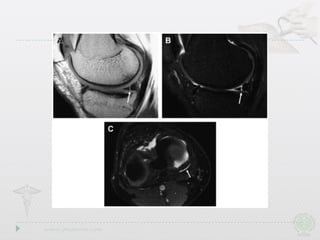

Radial Tears

Radial Tear

• Also involvefree edge,but path is perpendicular to long axis • Drastically affect ability to resist hoop stresses • Deeper the tear,the more drastic the biomechanical consequences Radial Tears